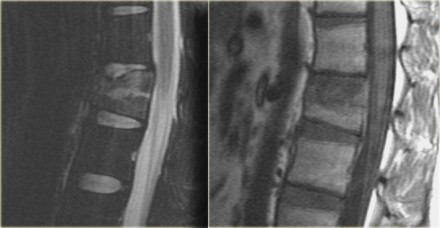

Sagittal T2WI and T1WI

The MR images show bone marrow edema in the involved vertebral body, but no additional soft tissue injury.

Based on the fact that the MR did not show any additional findings, this patient was treated as having a single column injury.

Consultation with orthopedic surgery recommended conservative management with a TLSO brace.

Nowadays there is a tendency to treat these thoracolumbar injuries conservatively, even if there is slight involvement of the middle column.

The role of MRI in these cases is not clear yet.